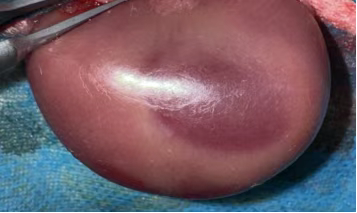

无创动脉夹夹闭肾动脉,观察肾脏转暗紫色,记录缺血时间(30-60min,可按需调整);

930ba3d6-16db-4763-9cb7-7a7e244a4958.png

松开动脉夹,待肾脏恢复红润(确认再灌注成功),逐层缝合,术后青霉素抗感染。